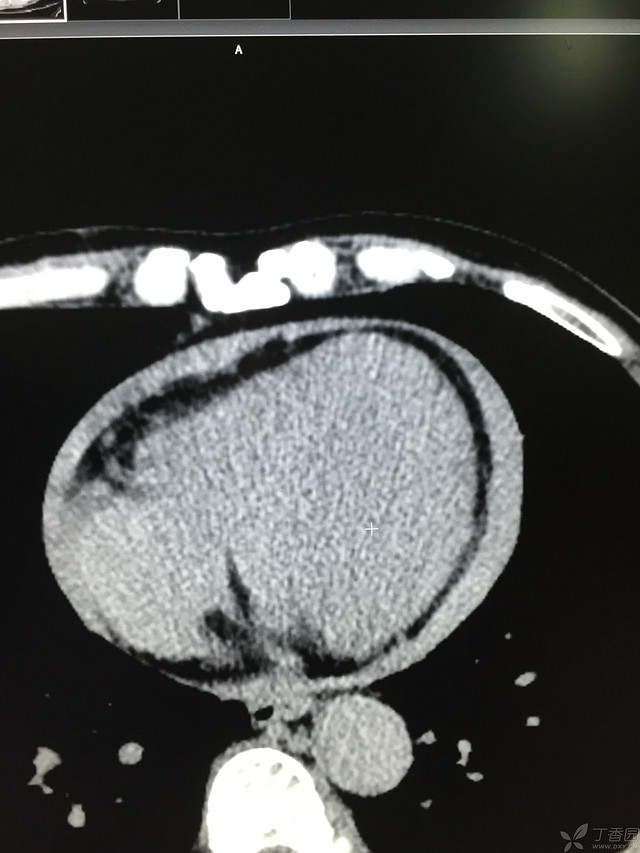

胸痛三天,加重三小时(CT是心包高密度影是什么)

患者性别:男

患者年龄:64岁

简要病史:三天前休息时突发胸前区疼痛伴大汗,到当地医院输液治疗后缓解,3小时前情绪激动后再次出现胸痛伴大汗,胸部压迫感,持续不缓解入院,到当地医院测血压180/?mmHg泵入硝酸甘油转入我院。

体格检查:血压94/72mmHg(右侧)96/74mmHg(左侧),心率78此/分,其他未见阳性体征